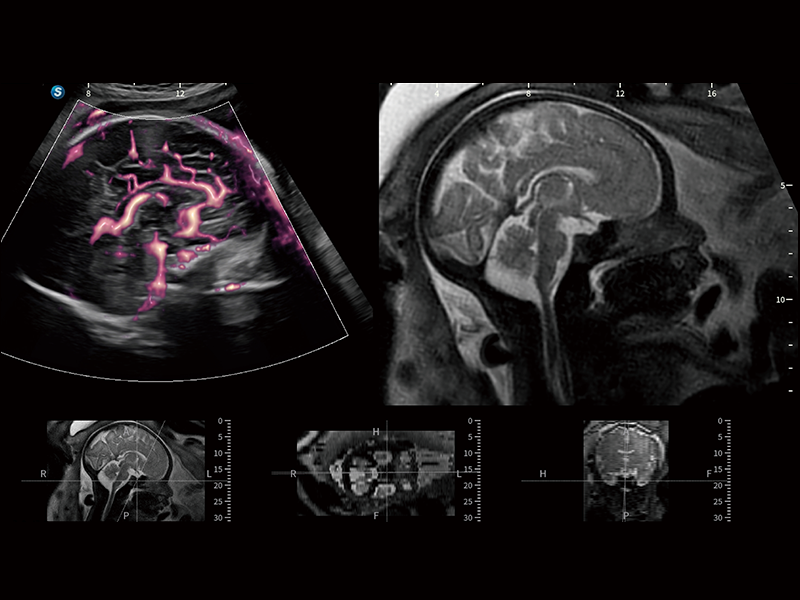

丰富的血流动力学检测技术,可在不同医疗场景中高效捕捉血流信号,助力临床诊疗。

在传统血流的基础上优化扫查和算法策略,能够更好的抑制组织信息,提炼红细胞运动信息,得到更高帧频,高灵敏度和分辨率的血流信号,还原更真实的血流动力学。

通过光照模型,使二维血流显示出立体的效果,增加血流的敏感性、成束性,减少外溢。可以和其他不同的血流技术联合使用,融合不同技术的优势。轻松应对微小血管,增强血流的立体效果,提升视觉敏感性。

通过创新的Matrix E自适应滤波算法,能有效滤除软组织和噪声信号,最大限度保留超低速微细血流的信号;结合超长时间域算法,极大提升细微血流的敏感性和空间分辨率,更真实的反应组织、包块的血流灌注情况。